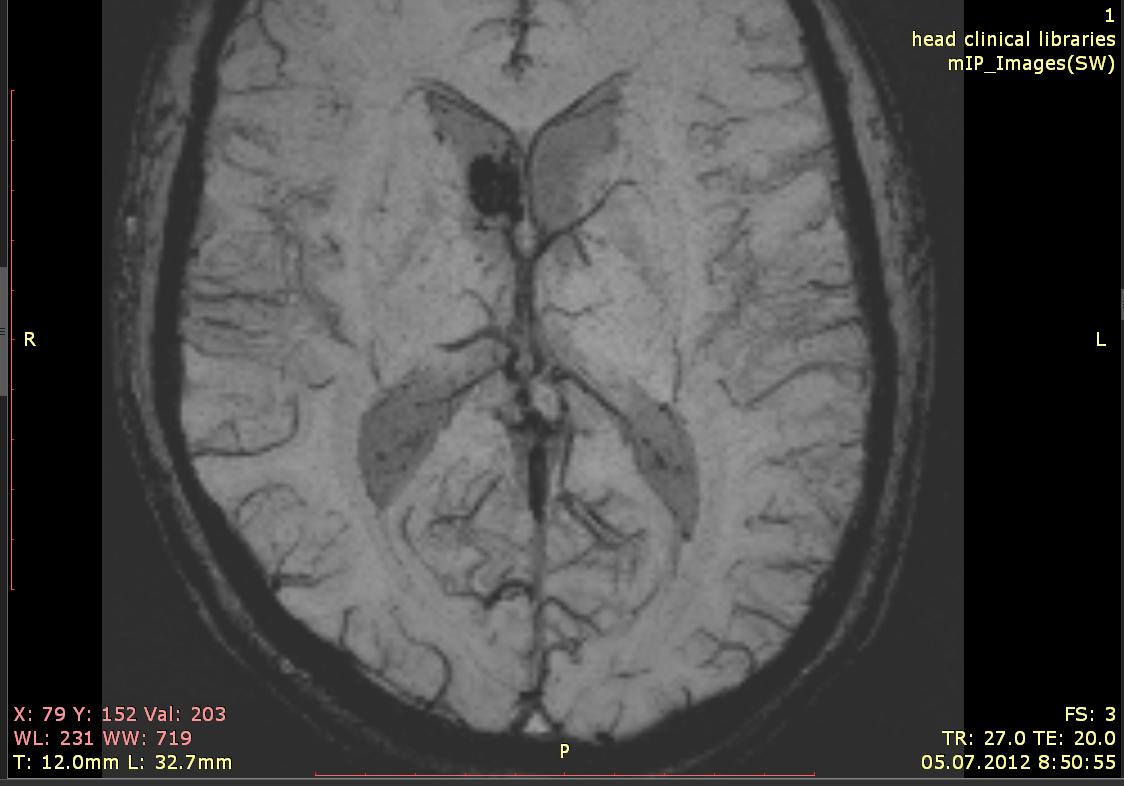

Можно ли где-то самостоятельно узнать, как интерпретировать MIP МРТ  головного мозга. Как правило, на этот вопрос отвечают: "вам это не надо" и прочее. Если есть ссылочка на литературу на эту тему, то был бы очень благодарен.

И если не сложно, то Ваши комментарии по этим снимкам без учета снимков в других проекциях и режимах. ( если по-делитантски, то что может давать черную область в данном режиме.спасибо )

Мрт и кт уже сделано 7 раз в течении полугода. был консультирован в нескольких больницах, в том числе и в Бурденко. Диагноз дифференцируется между: новообразованием, гематомой, кистой, каверномой, авм.

Было бы интересно всё посмотреть. На данной программе присутствуют следы изменённой крови, но она даёт плохое представление о локализации процесса. Для этого и делается несколько разных последовательностей в нескольких проекциях. А обучать Вас тут теории в индивидуальном порядке вряд ли кто будет. Хотя вот немного: МРТ в режиме изображений, взвешенных по неоднородности магнитного поля (SWI) Изображения, взвешенные по неоднородности магнитного поля (SWI), - это новый тип контраста МРТ, отличающийся от МРТ спиновой плотности, Т1 или Т2 визуализации. Этот метод использует разницу в чувствительности между тканями и применяет 3D радиочастотное градиентное эхо-сканирование высокого разрешения с полной компенсацией скорости. Эта особая форма сбора информации и обработки изображений дает изображение повышенной контрастности, чувствительное к венозной крови, кровоизлияниям и накоплениям железа. Она используется, чтобы повысить точность обнаружения и диагностирования опухолей, сосудистых и нервно-сосудистых заболеваний (инсульт и кровоизлияние, рассеянный склероз, болезнь Альцгеймера), а также показывает повреждения мозга после травм, которые нельзя диагностировать другими способами.

А MIP обычно называют алгоритм обработки изображений с целью выборки из них пикселей с максимальной интенсивностью для построения из них реконструкции: сосудов например или скелета с отсечением (грубо говоря) окружающих тканей.

Склонен считать, что на форумах как раз бывают именно такие люди, которые преданы своей профессии, поэтому и написал сюда с просьбой объяснить "на пальцах", почему допустим на мрт от 050712, которое приведено в самом верху, черная область считается кистой?

и там и там есть сигнал черного цвета. У края головы это видимо ликвор, а в области желудочков нечто, что имеет такой же сигнал.

Хотелось бы вот как то понять на данном типе снимков что еще имеет подобный сигнал? Судя по заключениям подобный сигнал может иметь опухоль или гематома может еще чтот....